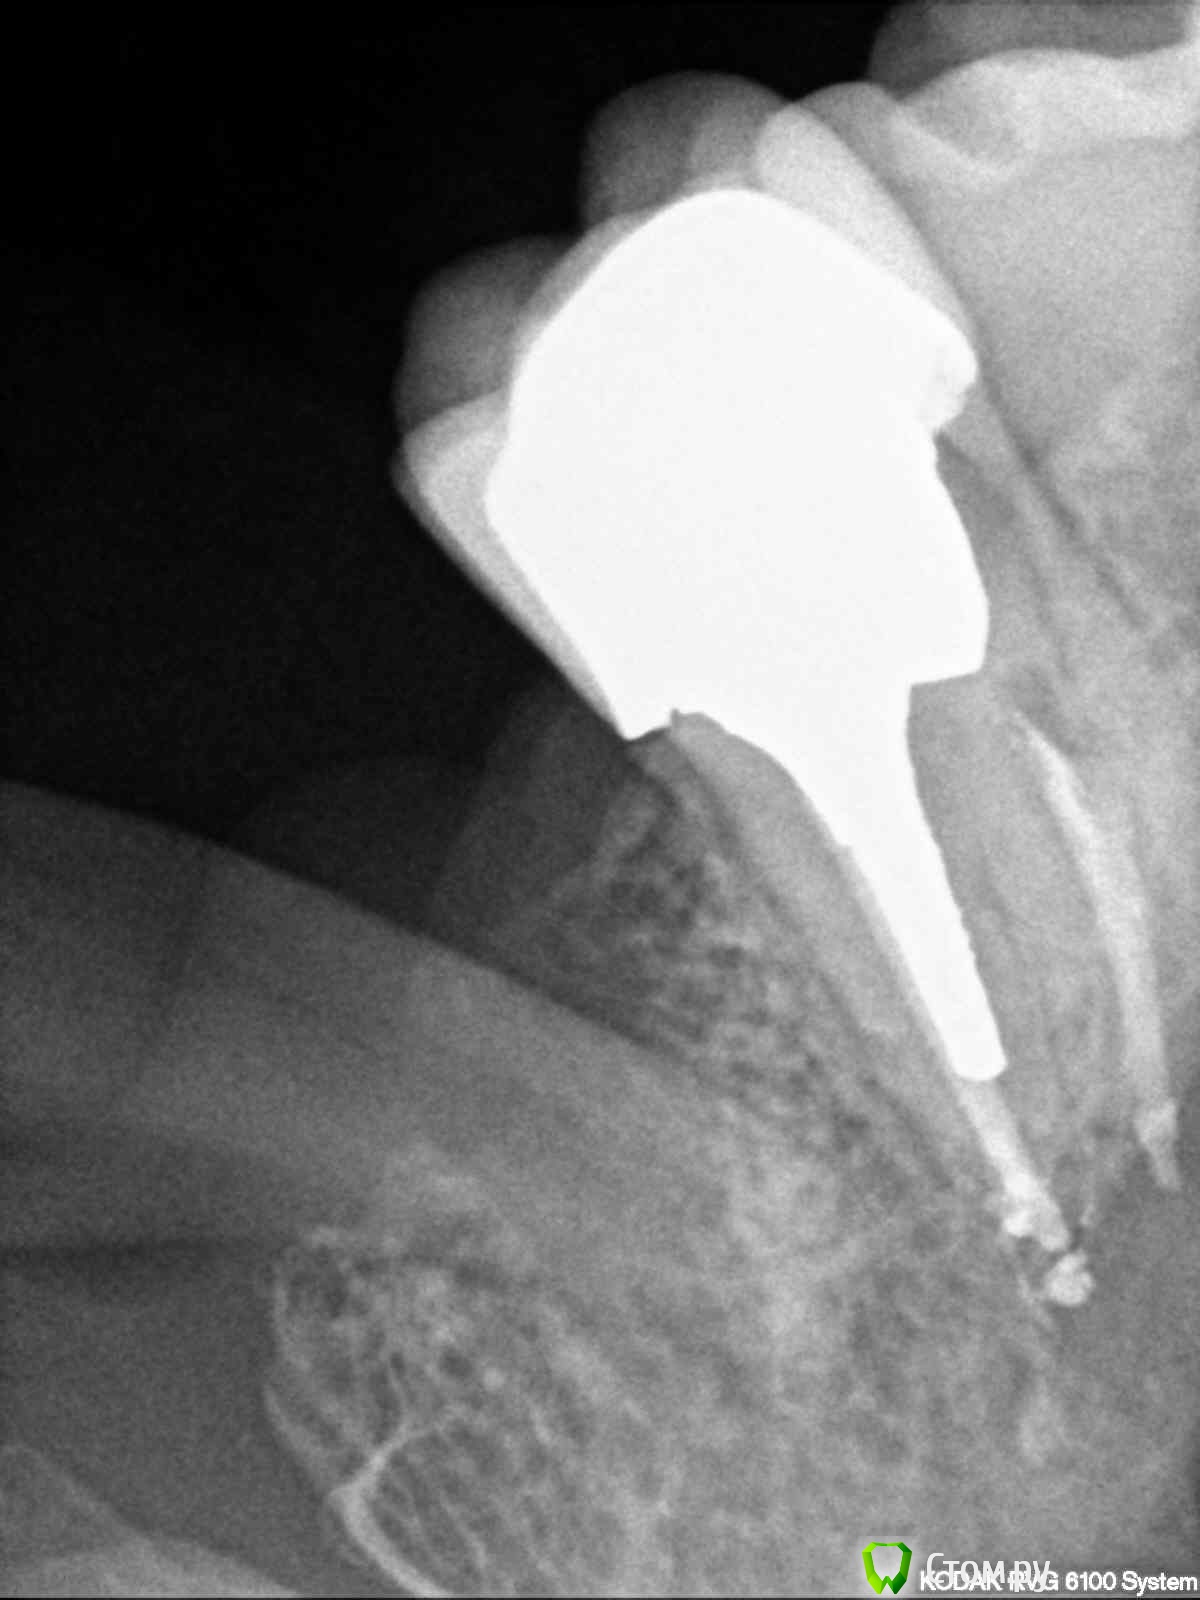

englishlady Опубликовано 6 ноября, 2013 Поделиться Опубликовано 6 ноября, 2013 Уважаемые врачи, оцените пожалуйста импланты. Меня стала беспокоить коронка на импланте 36. Хотелось бы понять, что не так до того как я пойду к врачу. Корнки на имплантах стоят на временном цементе. Десны не кровоточат. Заранее спасибо за ответ. Ссылка на комментарий

englishlady Опубликовано 6 ноября, 2013 Автор Поделиться Опубликовано 6 ноября, 2013 Опишите жалобы.Все выглядит не плохо.У меня стали ныть зубы слева вверху и внизу. На одном из форумов я получила консультацию по панорамному снимку. Там мне написали, что у импланта 36 нет остеоинтеграции. Там действительно меньше кости десны, поскольку имплант ставился через 5 месяцев после удаления. Особых жалоб нет, только периодически при промывании ирригатором с внутренней стороны в области 36 были неприятные ощущения. Еще несколько дней он как-то непонятно ныл. Может быть там остался цемент? На этом форуме у меня есть еще одна тема в терапии. Там еще есть вопросы. Но поскольку там мне никто не ответил, то я создала еще эту тему. Если я сделаю КТ, то стуация прояснится? Заранее спасибо за ответы. Ссылка на комментарий

red_butler Опубликовано 6 ноября, 2013 Поделиться Опубликовано 6 ноября, 2013 Лучше сделайте прицельный рентгеновский снимок области имплантации и фотоснимки Ссылка на комментарий

IvanK Опубликовано 6 ноября, 2013 Поделиться Опубликовано 6 ноября, 2013 Я бы советовалкоронку на 27 (на медиальной поверхности нарушено прилегание пломбы - может давать болевые ощущения).проверил 28 на предмет хр пульпита (кариес с медиальной контактной поверхности?)КТ - посмотреть на 38, на и на все остальное ... по цементу - послушает ортопедов. остеоинтеграцию можно проверить, обратитесь к Вашему хирургу Ссылка на комментарий